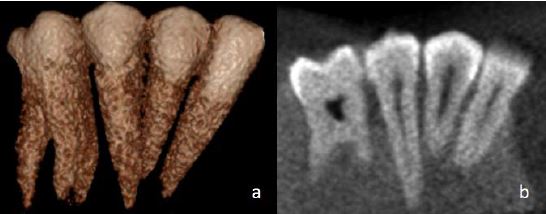

بررسی سن استخوانی به طو ر معمول در بیماران خردسال جهت ارزیابی رشد و به منظور تشخیص و مدیریت اختلالات اندوکرین و سندروم های کودکان انجام می شود. برای دهه ها تشخیص رشد و تکامل استخوانی با استفاده از بررسی رشد دست و مچ دست و به طور متداول با مراجعه به اطلس Greulich and […]